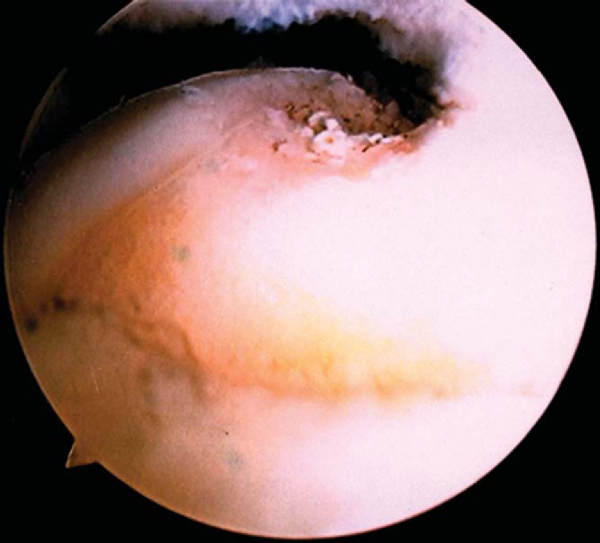

A routine diagnostic arthroscopy is performed. If any pathologic process is suspected in the ulnohumeral joint, a posterior portal is established to evaluate the ulnar and radial recesses. The radiocapitellar joint is evaluated for, among other entities, a soft tissue band or plica overriding the radius with pronation and supination, because this can be a cause of impingement. The lateral joint capsule and the insertion of the ECRB are assessed under direct vision. We prefer to grade ECRB involvement according to the grading suggested by Baker et al.[1]

3. Débridement of ECRB Origin and Release of ECRB

A thorough appreciation of the anatomy of the elbow, and of the ECRB in particular, is paramount to mastering this arthroscopic technique. The ECRB origin is extra-articular, thus requiring the resection of the capsule adjacent to the capitellum to visualize the ECRB origin. We prefer to perform the resection sequentially in four steps, resulting in a diamond-shaped resection zone (

Fig. 36-3

Step1: To visualize the ECRB, the overlying anterolateral capsule has to be removed, although in some patients, the capsule will already be torn, revealing the origin. The margins of the resection extend superiorly from the top of the capitellum to distally at the level of the midline of the radiocapitellar joint. If the resection extends farther distal than the midline of the radiocapitellar joint, the lateral collateral ligament is at risk.

Step 2: After adequate exposure has been obtained, we now turn our attention to resection of the ECRB origin. We start at the superior aspect of the capitellum, which represents the proximal and anterior margin of the resection. In a probing motion using a monopolar or bipolar radiofrequency probe, we resect the tendinous bands that represent the ECRB origin until we expose the red muscle fibers of the extensor carpi radialis longus.

Step 3: We then continue the resection anteroinferiorly. The posteroinferior border of the resection is marked by the lateral collateral ligament. One has to be careful to visualize the lateral collateral ligament. This is often easier once the semicircular fibers that cross from the lateral collateral to the annular radial ligament are visualized. Gravity inflow or the pump pressure can help with joint distention that separates the tendon from the lateral collateral ligament. The resection is performed under direct vision with the scope in the anteromedial portal (

Fig. 36-4